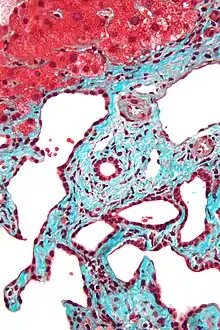

Micrograph of a bile duct hamartoma. Trichrome stain. Intermediate magnification